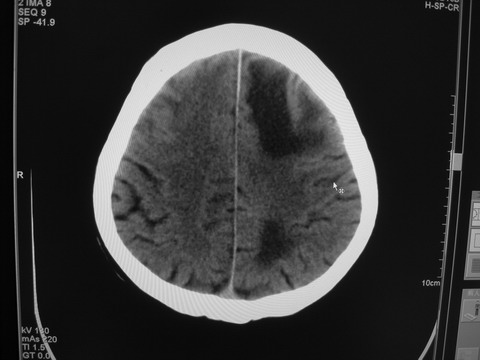

患者 男 69岁 头晕头痛不适

多发病灶,指状水肿,首先诊断转移瘤。

多个结节并周围大面积水肿区,多考虑多发性脑转移瘤

小病灶、大水肿,病灶多发,首先考虑多发转移瘤;建议查原发灶。

额顶叶多发小病灶、大水肿,首先考虑多发转移瘤;建议查原发灶

脑内多发病灶,小病灶,大水肿。

典型转移性肿瘤。

应进一步检查,查找原发病灶。

结果 : 该患者结肠癌病史5年 考虑脑转移